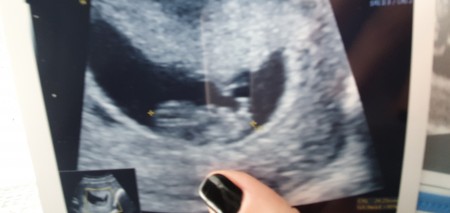

image

Gebelik haftası 8+6